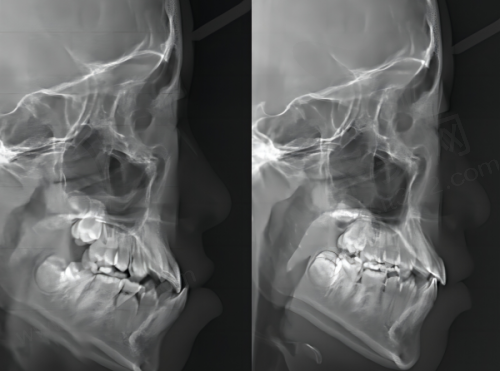

正颌手术

双鄂手术